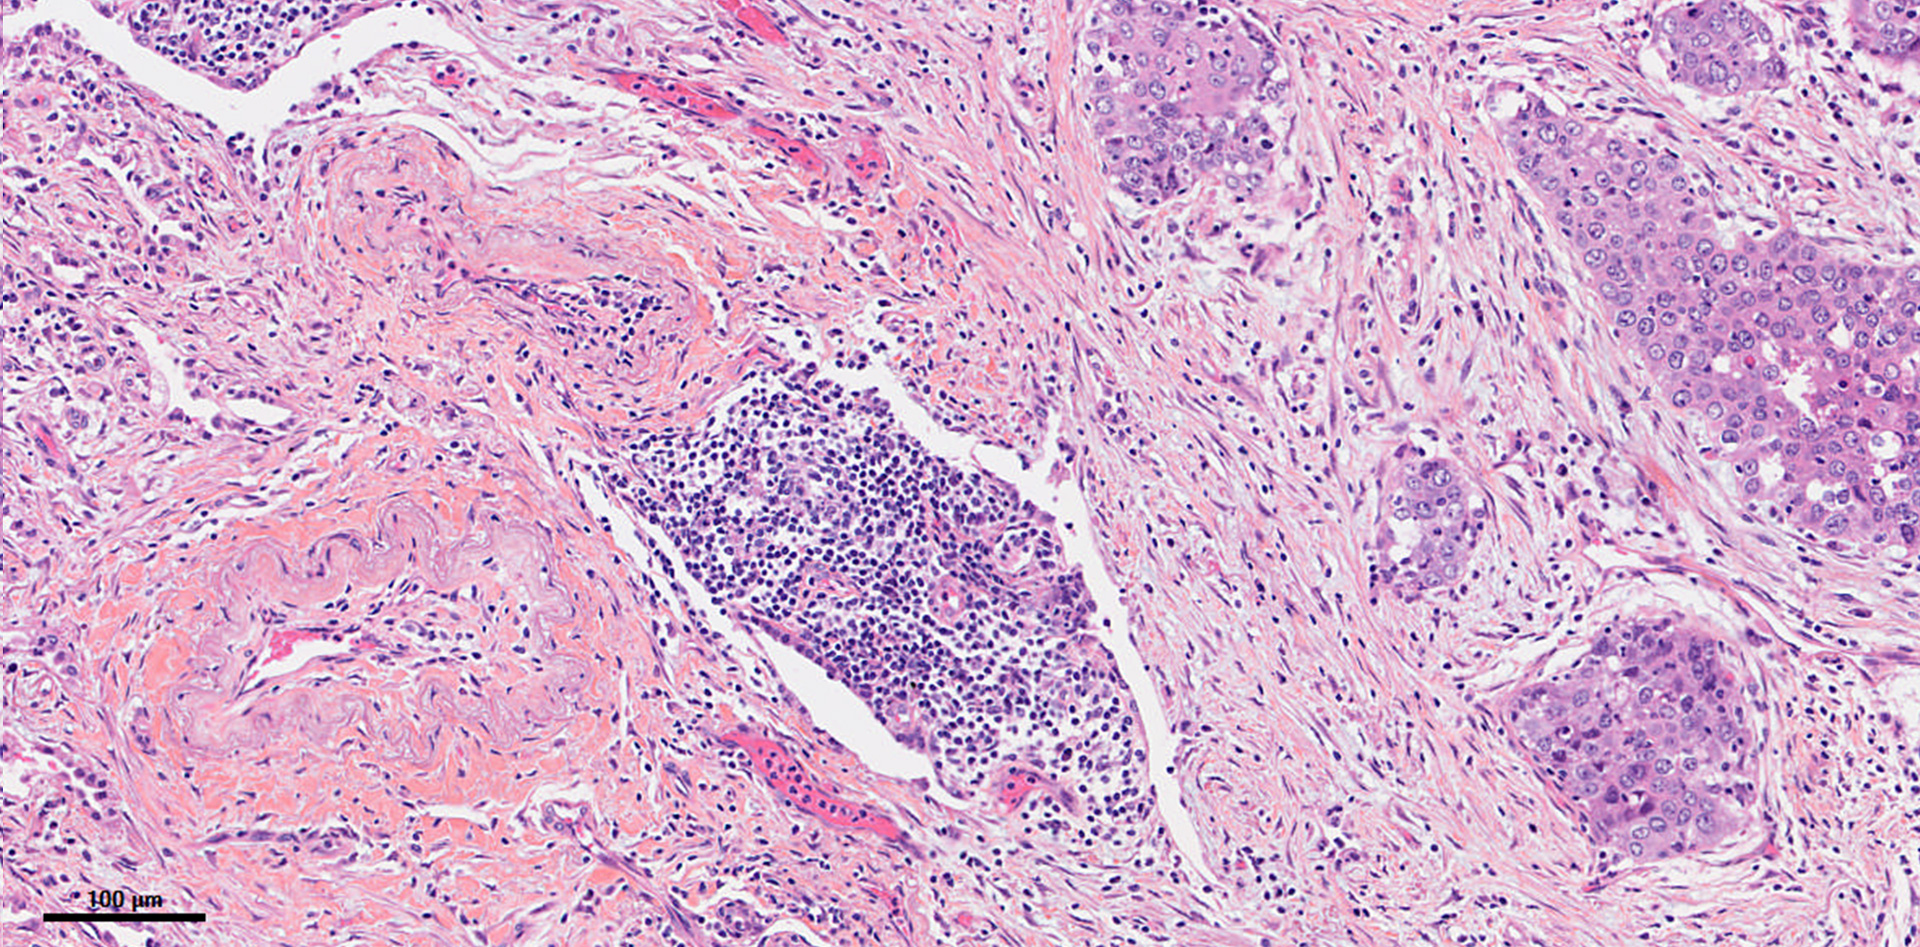

Illustration of a mature TLS detected in a primary pancreatic adenocarcinoma.

This panel shows representative examples of immature and mature TLS observed in tumor samples. The pictures from the left to right column correspond to 1) Hematoxylin Eosin Saffron (HES) staining, 2) Double immunohistochemistry staining of CD3/CD20 (CD3 in brown, CD20 in purple), 3) Multiplex immunofluorescence assay of CD4 (blue), CD8 (yellow), CD20 (orange), CD21 (green) and CD23 (pink). The scale bars on the HES images indicate 50µm and 100µm for the upper and lower panels, respectively. Black cropped arrows highlight the tumor cells in the samples.